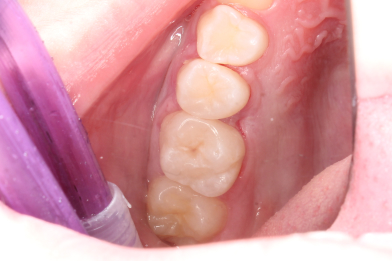

Жалобы на застревание пищи между зубами 26,25, реакция на сладкое и

Колиш Максим Петрович

холодное.

При осмотре обнаружен контактный кариес на зубах 26,25.

Лечений в один визит , восстановление функциональности композитной

реставрацией. -